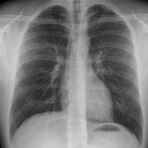

Konventionelles Röntgen

Der Begriff Röntgen, oder auch Röntgendiagnostik bezeichnet ein Verfahren in der Radiologie, bei dem von einer Röntgenröhre elektromagnetische Wellen (Röntgenstrahlen) durch die zu untersuchende Körperregion des Patienten gesendet werden. Je nach Dichte der Gewebeart des Körpers (z.B. Knochen oder Lunge) werden die Röntgenstrahlen im Körper unterschiedlich stark abgeschwächt. Ein digitaler Detektor empfängt dann die Röntgenstrahlen, die in abgeschwächter Form den Körper wieder verlassen haben. Daraus wird das Röntgenbild erzeugt.

Die Röntgenuntersuchung ist weiterhin eine unverzichtbare Basisdiagnostik. Viele Fragen können in der medizinischen Diagnostik mit einer konventionellen Röntgenaufnahme geklärt werden.